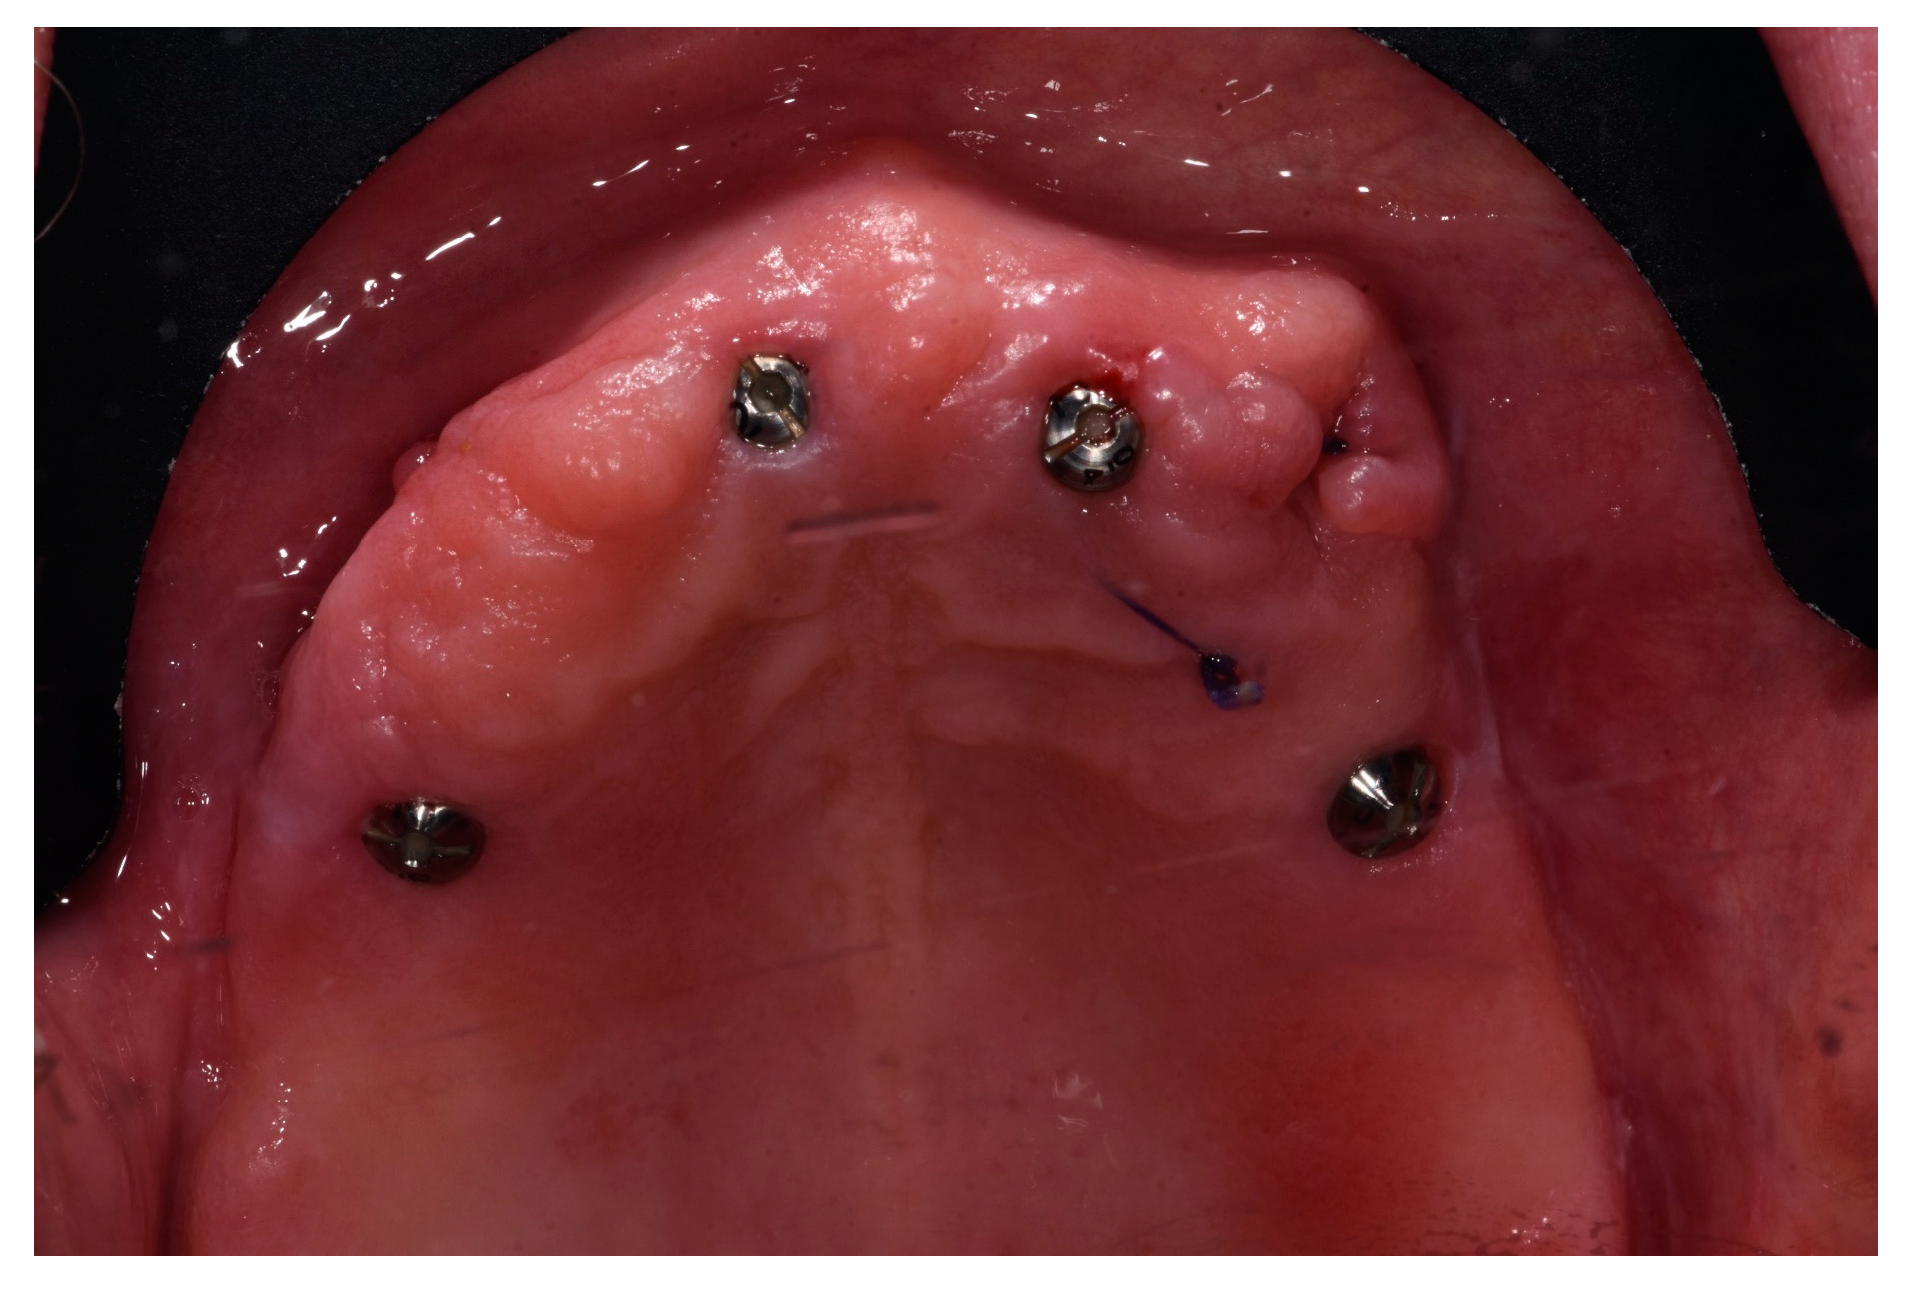

2. Materials and Methods

2.2. Surgical Procedures and Post-Operative Care